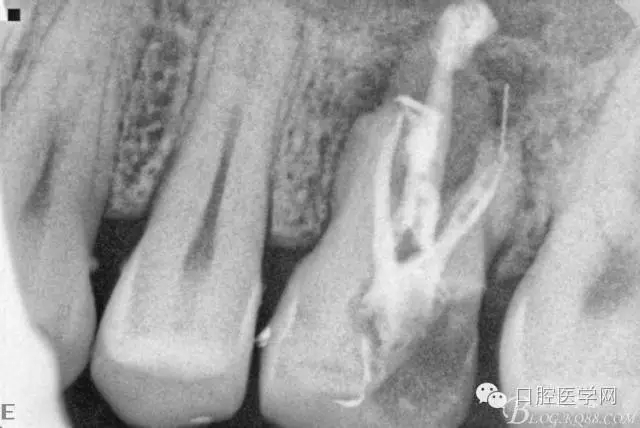

四個(gè)月后患牙Ⅰ°松動(dòng)明顯好轉(zhuǎn),根管內(nèi)無異物,可行根管充填。試主尖片。

根管充填后(遠(yuǎn)頰根內(nèi)有一斷針)。